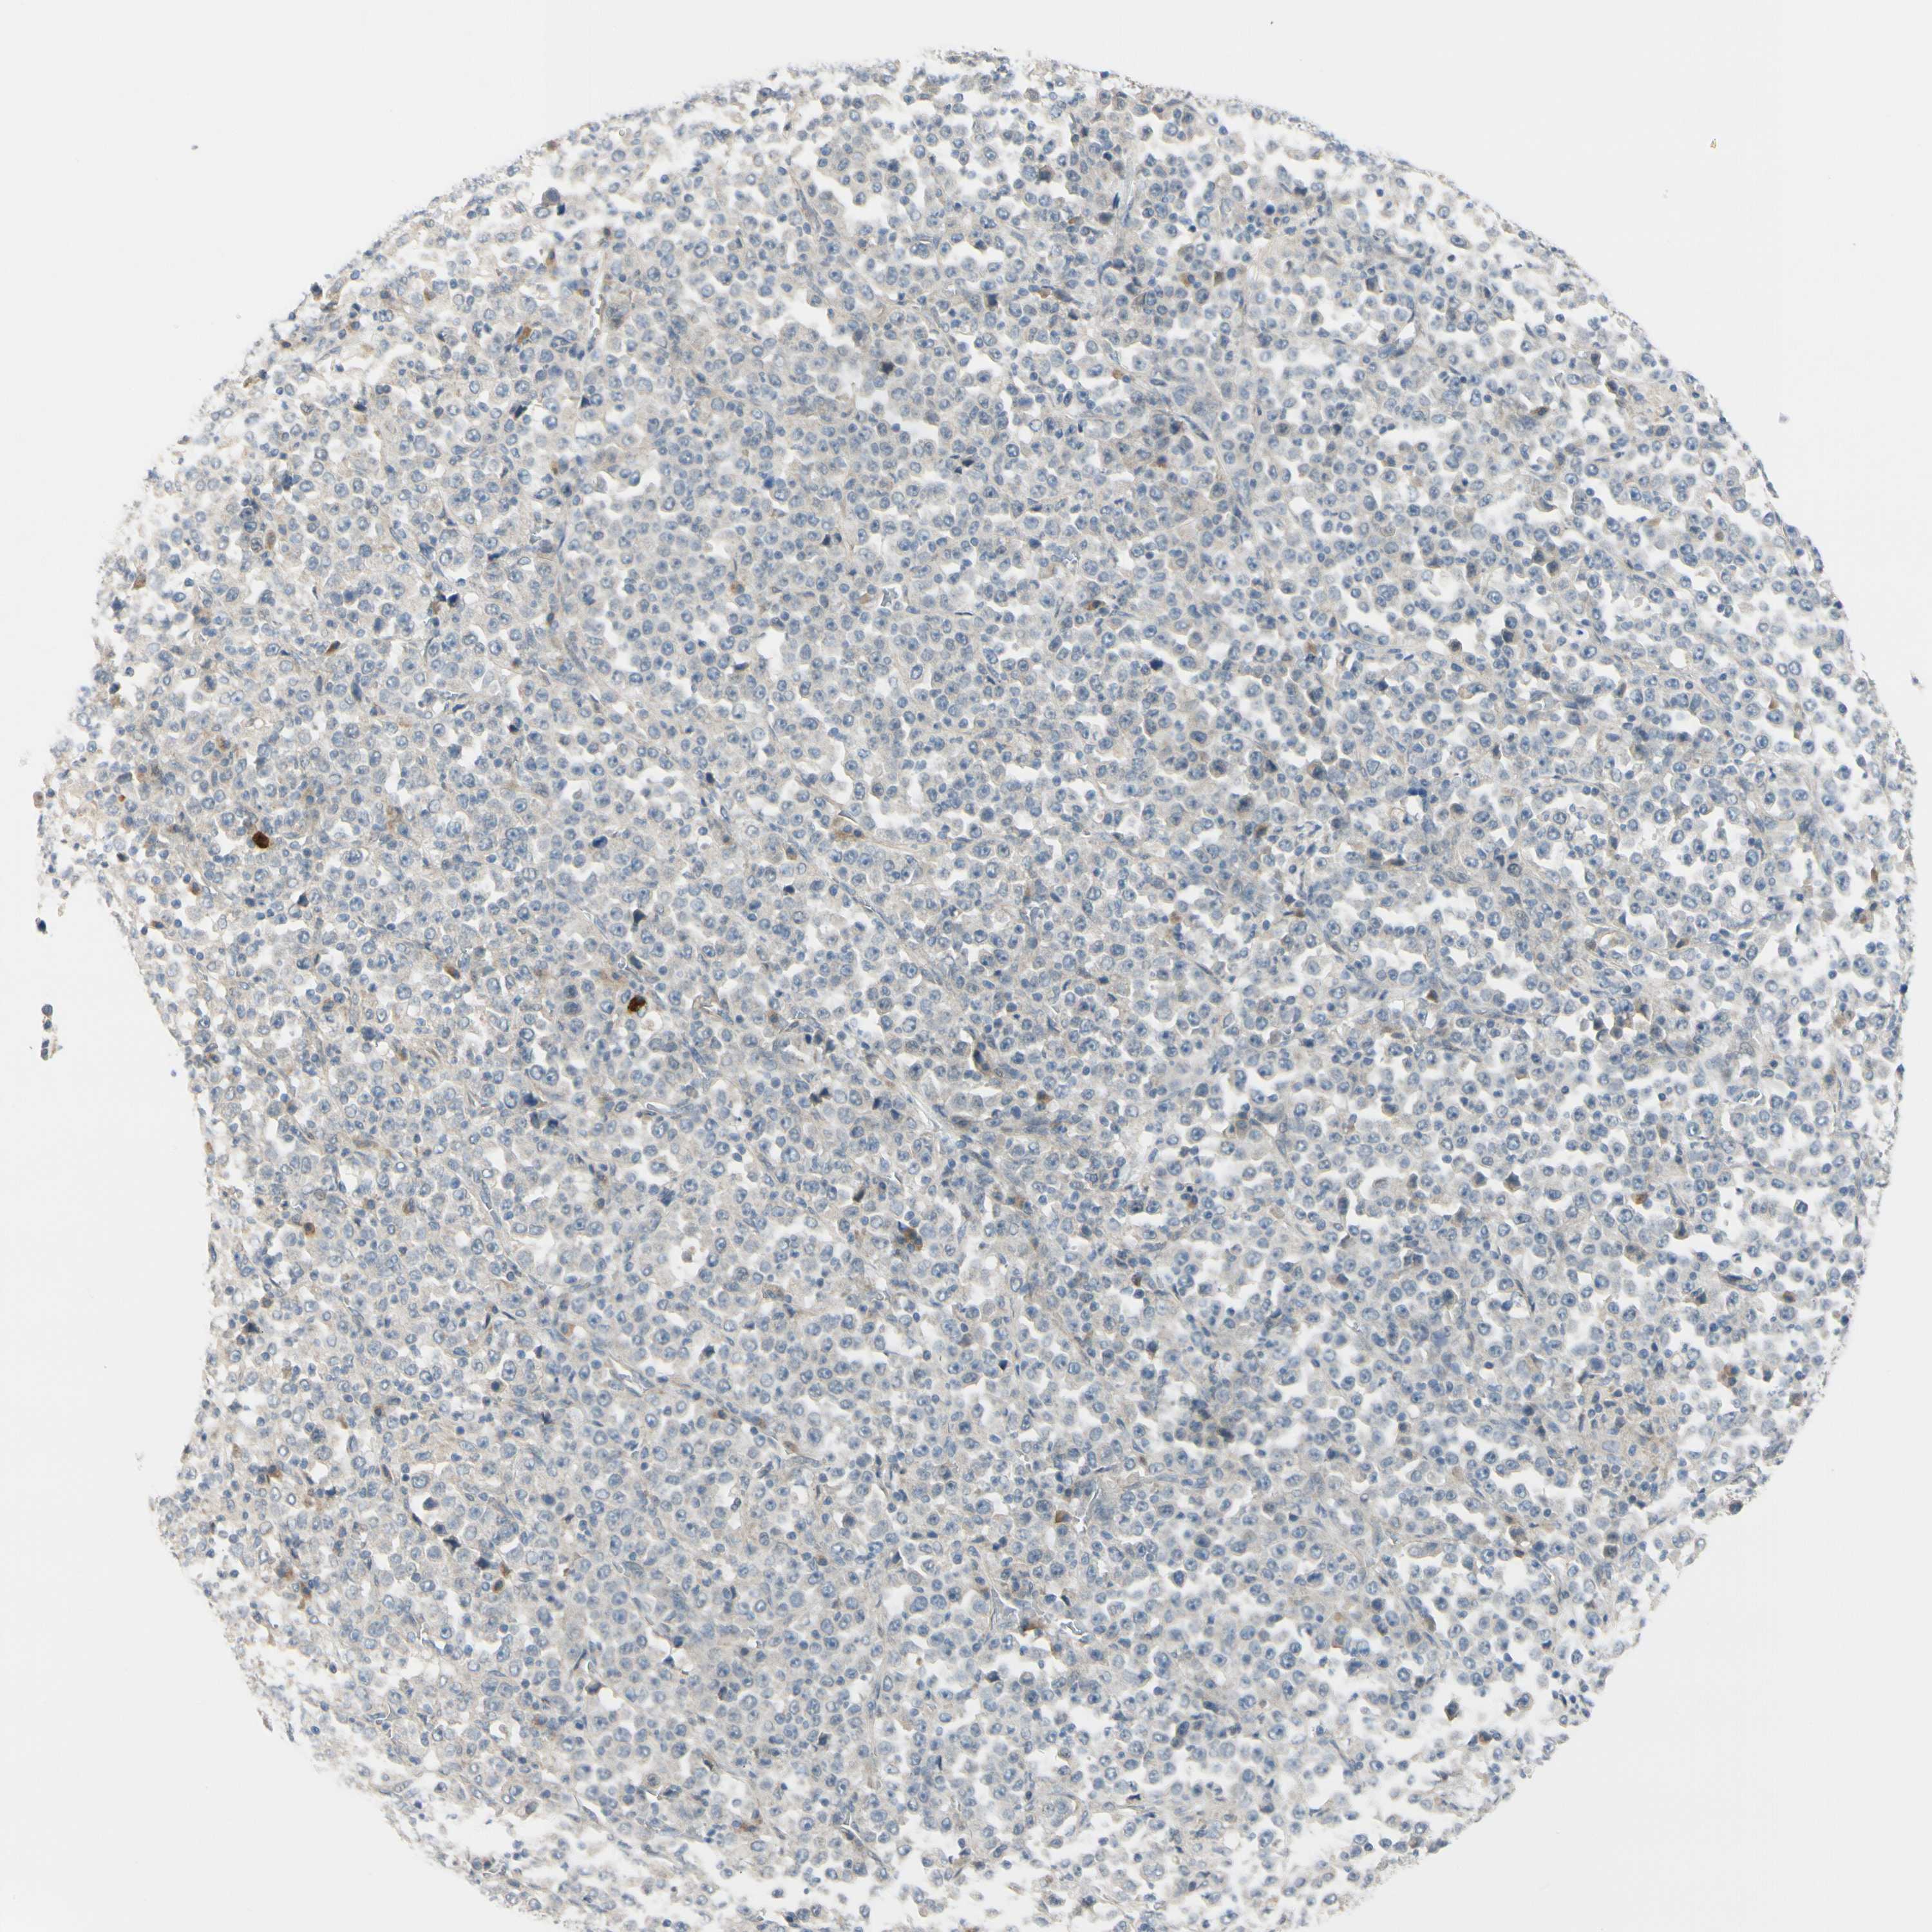

STOMACH CANCER - Protein expressioni

A mouse-over function shows sample information and annotation data. Click on an image to view it in a full screen mode. Samples can be filtered based on level of antibody staining by selecting one or several of the following categories: high, medium, low and not detected. The assay and annotation is described here.

Antibody stainingi

Antibody staining in the annotated cell types in the current human tissue is reported as not detected, low, medium, or high, based on conventional immunohistochemistry profiling in selected tissues. This score is based on the combination of the staining intensity and fraction of stained cells.

Each image is clickable and will lead to virtual microscopy that enables deeper exploration of all samples and also displays staining intensity scores, fraction scores and subcellular localization as well as patient and tissue information for each sample.

Antibody HPA005922

Antibody HPA006028

Antibody CAB008368

Staining

High

Medium

Low

Not detected

Intensity

Strong

Moderate

Weak

Negative

Quantity

>75%

75%-25%

<25%

None

Location

Nuclear

Cytoplasmic/membranous

Cytoplasmic/membranous,nuclear

Adenocarcinoma, NOS

Adenocarcinoma, High grade